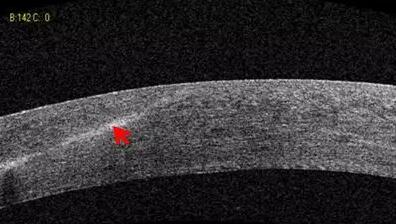

白内障篇

1:白内障混浊晶体观察

2:人工晶体位置观察